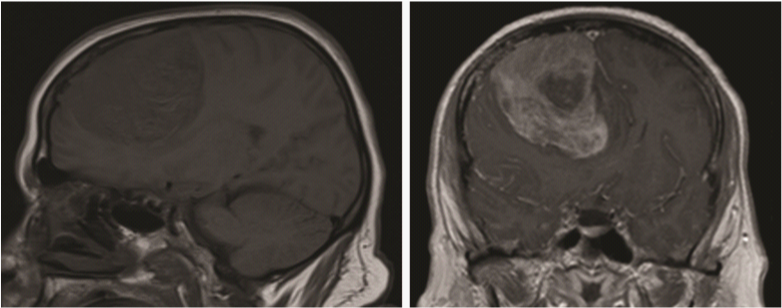

On arrival to our intensive care unit, seizure activity was noted and the patient was loaded with phenytoin and hyperosmotic therapy was initiated. Sudden deterioration earlier was thought to be due to a post-ictal state. An urgent MRI was more in favor of parasagittal meningioma (Figure 1). Her exam improved to localizing on the right and eye opening. Owing to significant mass effect that contributed to drop in her neurological status, we opted to intervene surgically for the sake of decompression and control of her intracranial hypertension and obtaining samples for pathological diagnosis.

Figure 1 Cerebral MRI demonstrating large parasagittal meningioma. Note that the superior sagittal sinus is spared from tumor invasion.